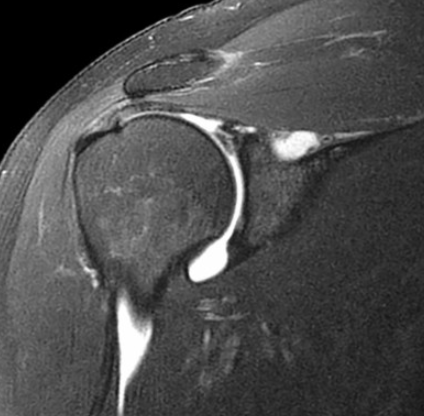

Adhesive Capsulitis

• Capsule thickening and edema

• IGHL ligament thickening, typically >4 mm

• Soft tissue thickening of the rotator cuff interval

• Loss of fat here

• T2 hyperintense & enhance

• Coracohumeral ligament thickening (> 4mm)

• Decreased capsular volume

• Axillary recess appears small

• Basically no fluid around shoulder and the tissues adhere close to the humerus bone

• Unless concurrent other shit the rotator cuff itself and labrum are normal